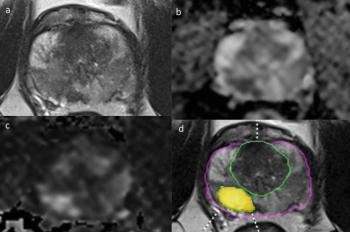

Examining the use of the Response Evaluation Criteria in Prostate-specific Membrane Antigen (PSMA) PET/CT (RECIP 1.0) model for assessing the treatment of metastatic castration-resistant prostate cancer, researchers found robust agreement between quantitative application of RECIP via tumor segmentation software and qualitative application of the model through reads by nuclear medicine physicians.